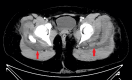

Figure 2. Axial post-contrast CT of the proximal lower extremity musculature

Axial contrast-enhanced CT demonstrates bilateral gluteal muscle enlargement, muscle edema, and heterogeneous muscle enhancement. Arrows mark hypodense areas within the heterogeneous enhancement of the muscles.